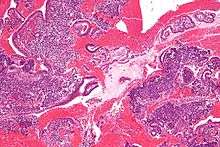

High magnification micrograph of decidualized endometrium due to exogenous progesterone (oral contraceptive pill). H&E stain

Low magnification micrograph of decidualized endometrium. H&E stain